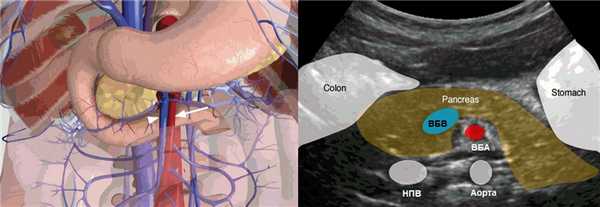

Рисунок. На УЗИ нормальное взаиморасположение ВБВ и ВБА.

Рисунок. На первом снимке ВБВ (треугольник) лежит справа от ВБА (стрелка) — норма, на втором снимке ВБВ (треугольник) спереди от ВБА (стрелка) — незавершенный поворот средней кишки.